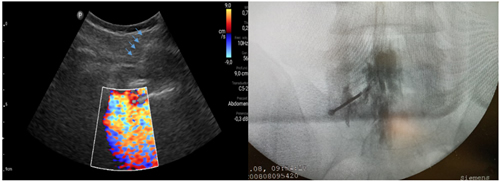

Pacientes y métodos: Un total de 25 pacientes con dolor radicular lumbosacro fueron seleccionados para recibir inyecciones epidurales interlaminares de esteroides en posición decúbito dorsal, utilizando la técnica ecoguiada en plano, en tiempo real, en eje corto o transversal. En todos los casos, un epidurograma de control fue realizado previo a la inyección de la solución de esteroides. El rendimiento de la técnica fue estudiado mediante la tasa de éxito de la misma, entendido como éxito a la obtención de un epidurograma sin necesidad de abandonar la técnica ecográfica en un tiempo menor a 10 minutos. El rendimiento del procedimiento fue estadísticamente evaluado por el método de la suma acumulativa (CUSUM), y la curva de aprendizaje aplicando este método fue construida.

Resultados: La distancia promedio desde la piel al complejo posterior evaluada por el escaneo ecográfico previo al procedimiento fue de 6,7 ± 1,8 cm. De los 25 procedimientos realizados, en 21 se alcanzó el espacio epidural sin ayuda de la fluoroscopia, en un tiempo promedio de 4,8 ± 1,2 minutos. Esto constituye una tasa de éxito del 84 %. En los cuatro procedimientos restantes el espacio epidural fue alcanzado con éxito mediante el uso complementario de la fluoroscopia.

13. Riveros-Perez E, Albo C, Jimenez E, Cheriyan T, Rocuts A. Color your epidural: color flow Doppler to confirm labor epidural needle position. Minerva Anestesiol. 2019;85(4):376-83.

14. Yoon JS, Sim KH, Kim SJ, Kim WS, Koh SB, Kim BJ. The feasibility of color Doppler ultrasonography for caudal epidural steroid injection. Pain. 2005;118(1-2):210-4.

Figura 2